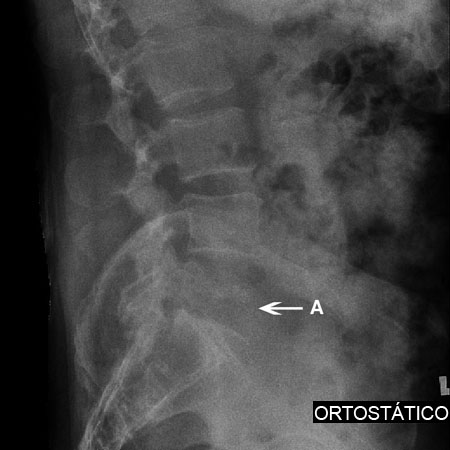

Radiografia de uma fratura de compressão: uma radiografia de perfil de uma fratura de compressão L2 (A). Observa-se um formato em cunha do corpo vertebral

Cortesia do Dr K. Singh; usado com permissão